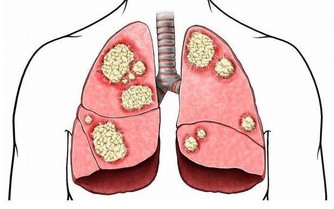

一說起尿毒症可能大家現在都不太陌生,尿毒症是指身體不能通過腎臟產生尿液,把身體代謝所產生的廢物,還有多餘的水分排出體外而引起的毒害,尿毒症是腎功能下降

有疾病放任不管

很多人認為身體出現的是小問題就無關緊要,沒有從根本上解決,隨著疾病的不斷發展,小的問題會逐漸嚴重,

如果意識到正確應對疾病的重要性,

結語:尿毒症對身體的傷害是毀滅性的,目前的醫療水平無法徹底根治尿毒症。那麼我們就應該防患於未然,改變不良的生活習慣,這樣才能更好的保護自己的腎臟。